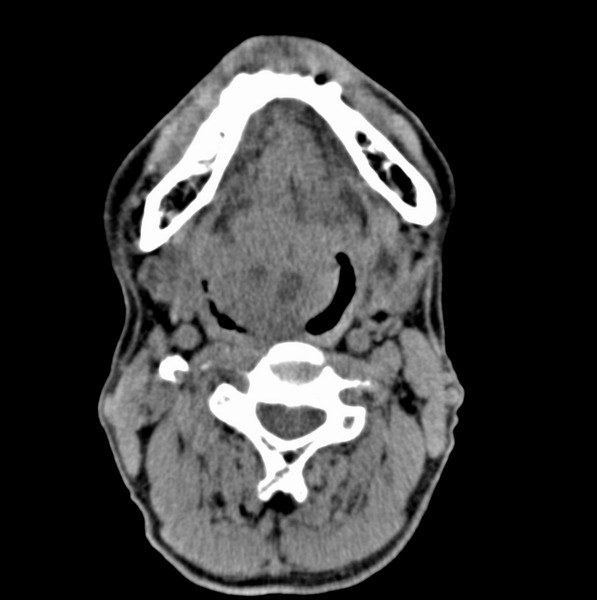

男、60、舌根肿物。

舌垂直肌和横肌影处肿块影,边缘不规则,咽腭扁桃体及舌下间隙脂肪影消失,病变侵及口咽。

考虑-----舌根癌

舌跟软组织肿块,较大有坏死,钙化。结合年龄一般是恶性肿瘤。

舌根部较大软组织肿块,其内见坏死低密度区及钙化影;考虑舌根癌可能。